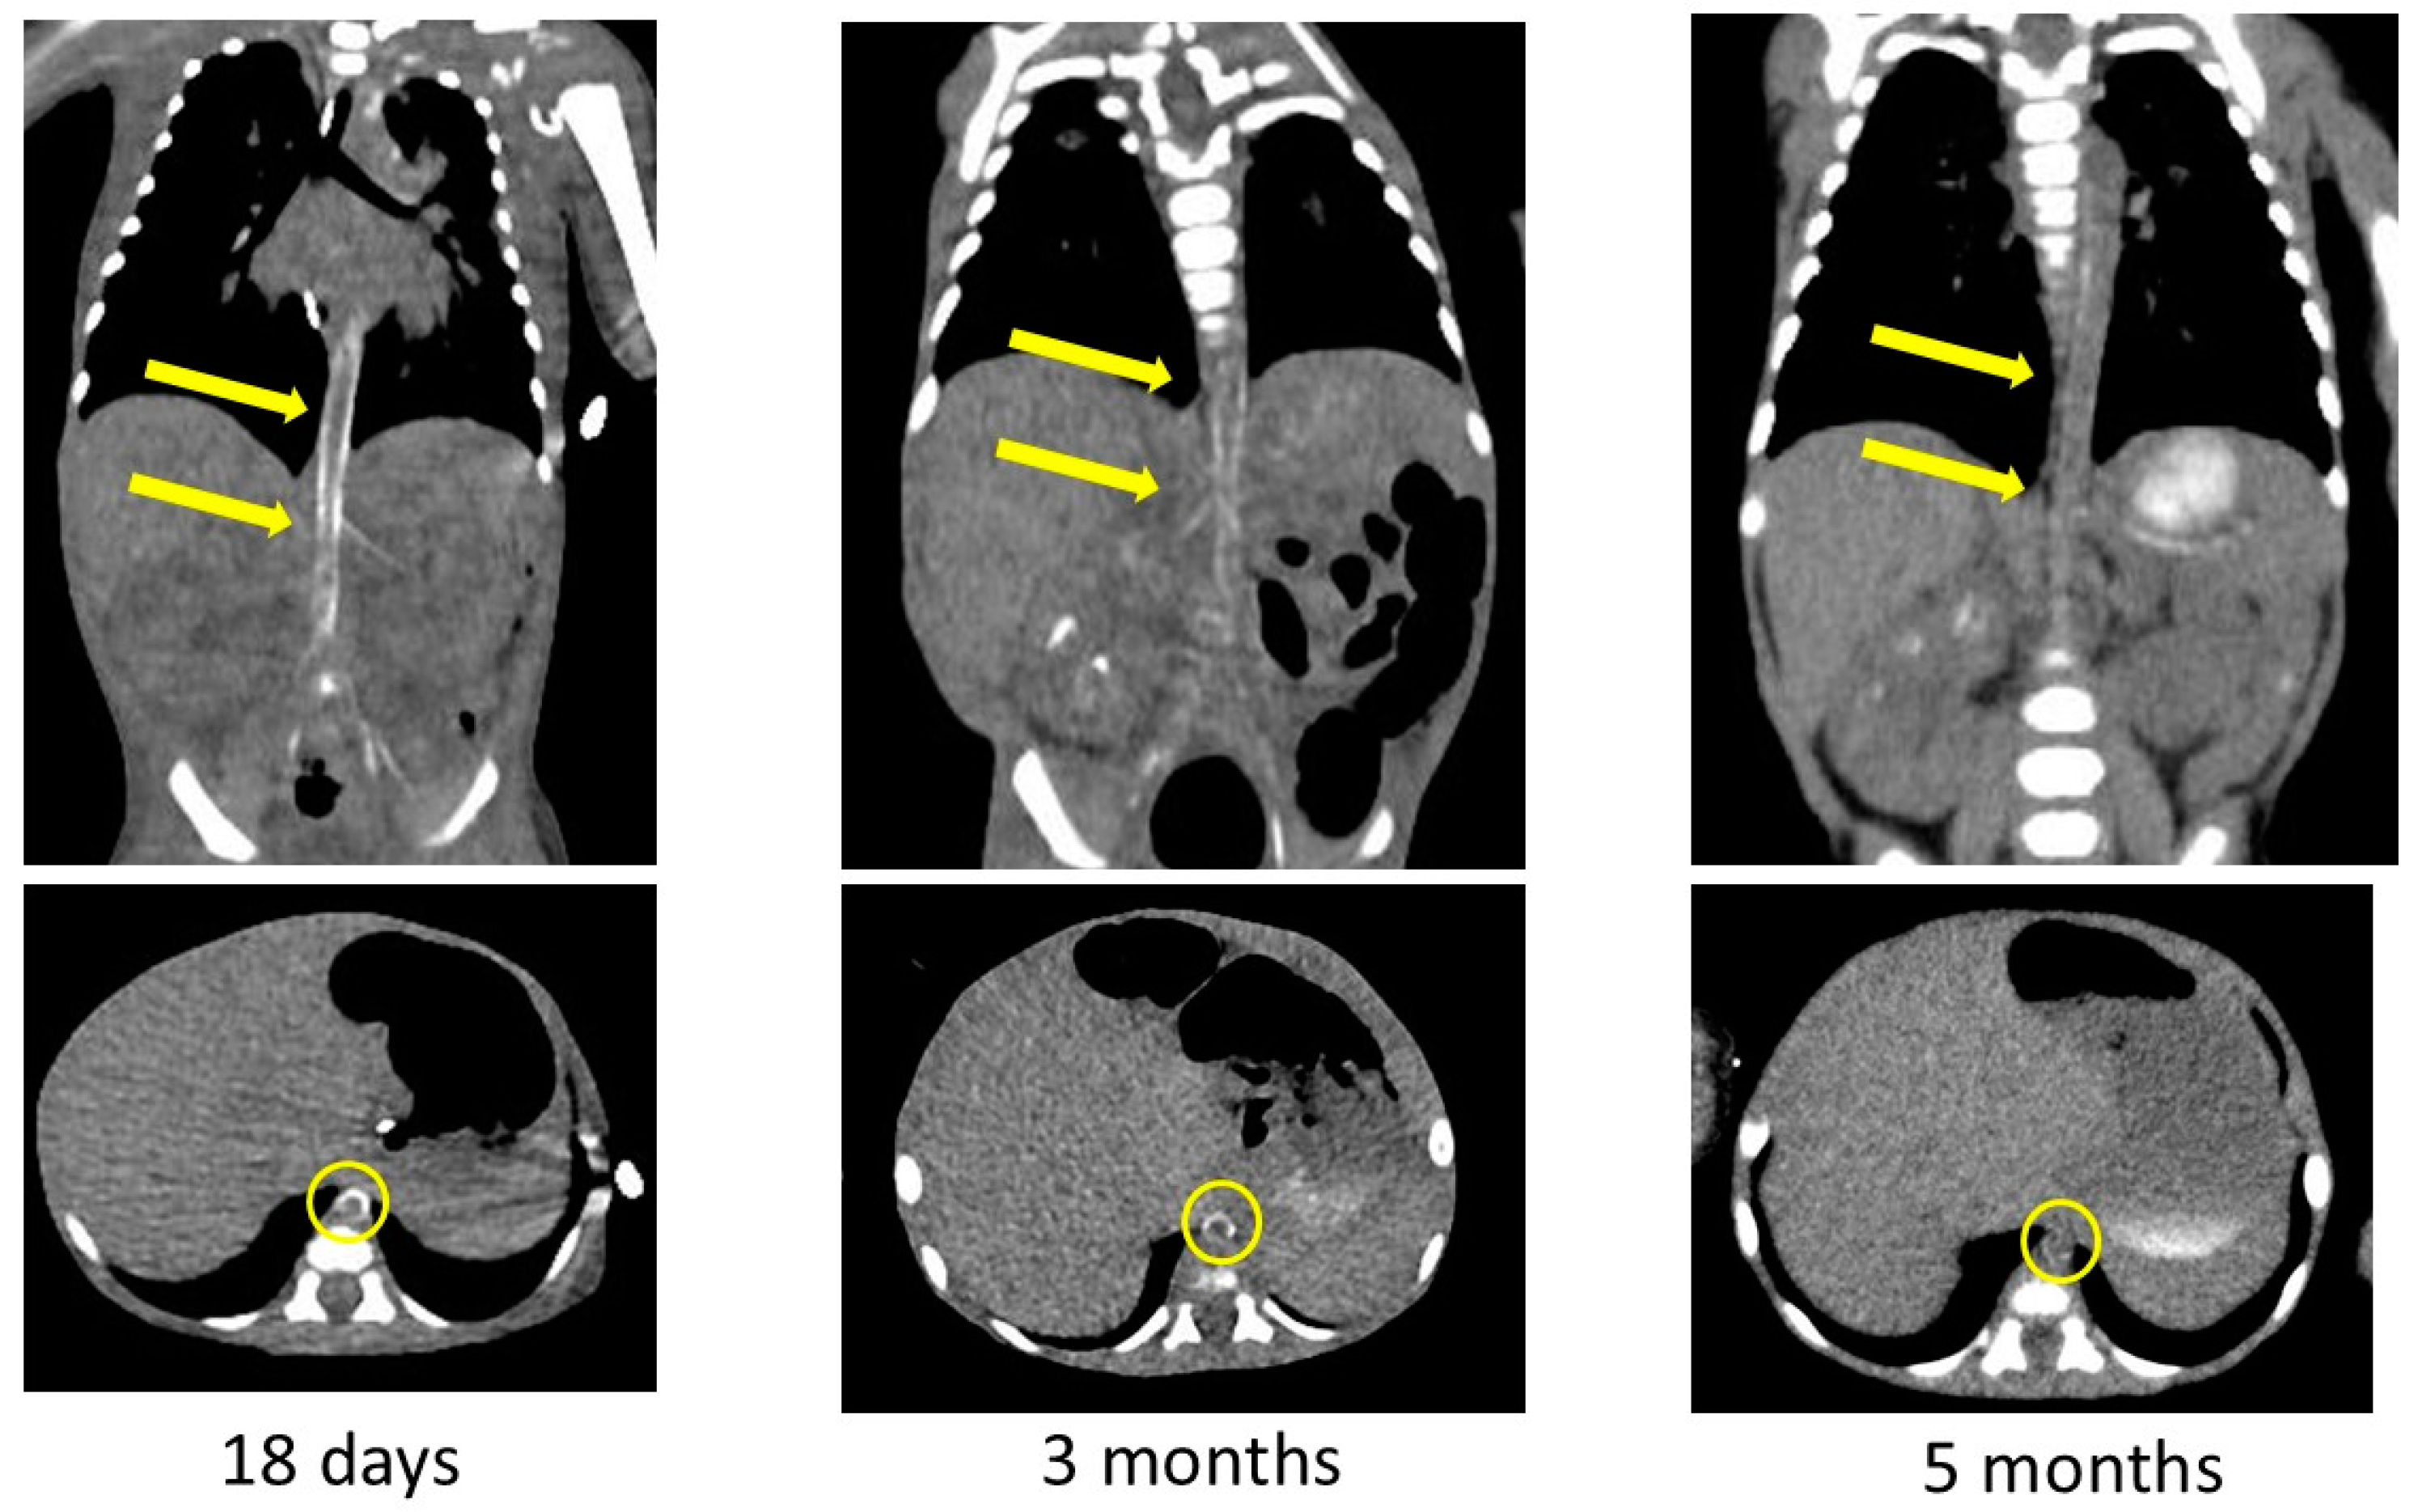

2. Case Presentation